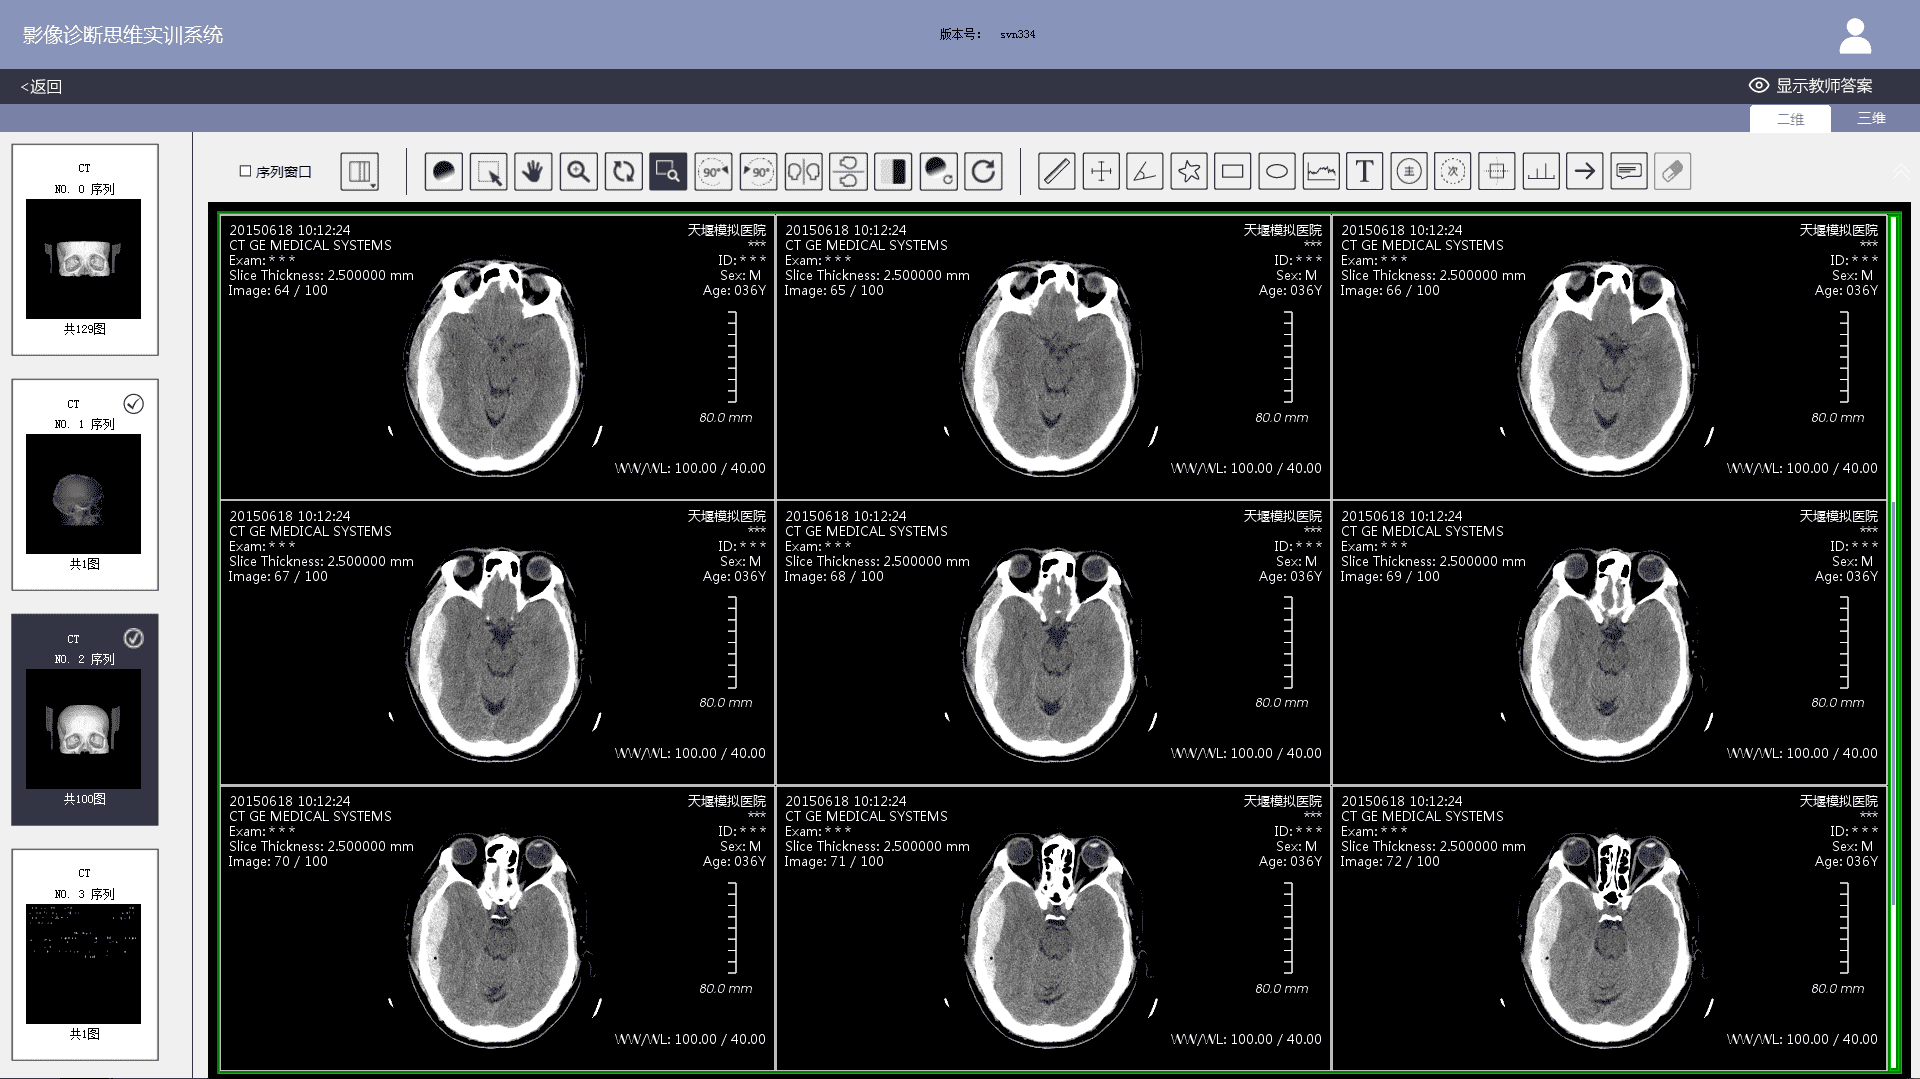

3)  Imaging workstation: The system comes with an imaging workstation and all cases can be loaded with DICOM files. Teachers can post-progress them according to actual teaching needs. The post-processing function meets the basic requirements of a common clinical imaging workstation, including: 1) layout. Users can choose 1X1, 1X2, 2X1, 2X2, 2X3, 3X3, etc.; 2) Window width and level adjustments; 3) Zoom in and out; 4) Zoom in on the area of interest; 5) Left turn 90 degrees; 6) Right turn 90 degrees; 7) Left and right mirror flip; 8) Up and down mirror flip; 9) Negative film; 10) Distance measurement; 11) Two-way ruler; 12) Angle measurement; 13) Polygon measurement; 14) Adding notes & comments; 15) Labeling major signs; 16) Labeling secondary signs, etc.

3)  When viewing case images, students can post-process DICOM files on the imaging workstation to observe positive and negative imaging signs in greater detail. After finishing a case exercise, student's test results, the correct diagnosis report and the comparison of the thinking processes will show. Students can also participate in image thinking case assessment set up by teachers.